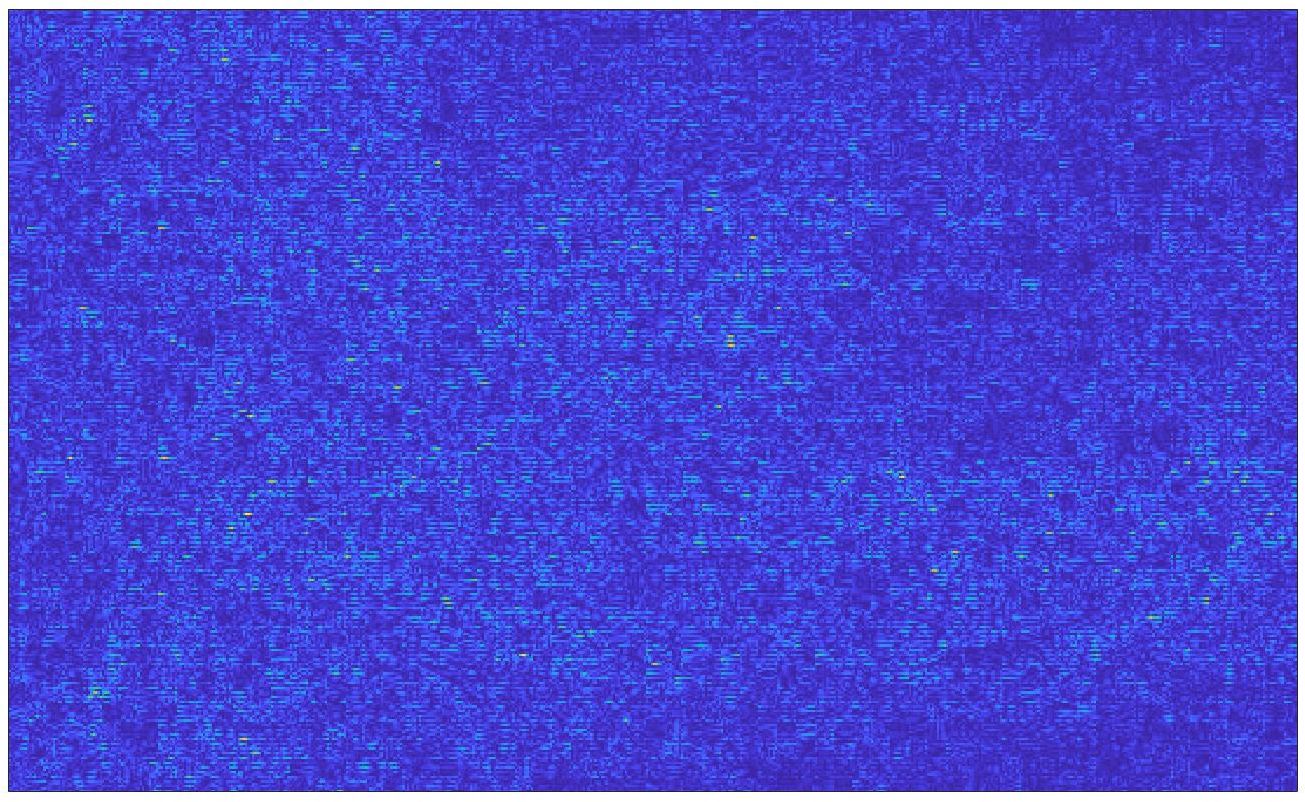

Our framework visually improves the results, in terms of blurring and artefacts. This result is more evident in the magnification of the ear of the foetus (Fig. 3), the mitral valve (Fig. 4), and the mass edges (Fig. 5). Fig. 6 shows the error image of the three anatomical districts with both 2X and 4X up-sampling factors, with the maximum error in the scale . The error is more evident in the contours of the anatomical structures; moreover, the abdominal district shows a smaller error than the cardiac and obstetric ones. We underline that the view for each image is scaled to its maximum, to improve the visualisation of the error.

The analysis of the absolute value of the difference between the input and the prediction of the network (Fig. 9) shows that the alteration of our prediction to the pixel values ranges from 0 to a maximum absolute value of 20, mainly located on the edges of the anatomical structures; furthermore, the black uniform areas are less affected by the prediction. In terms of the distance between the input and the prediction, we do not observe a significant difference among anatomical districts and between 2X and 4X up-sampling.

We address both the comparison among state-of-the-art algorithms that are used for the selection of the up-sampling method of our framework and the comparison of our results with previous work. Among up-sampling STAR methods, we test four methods belonging to different classes: Cubic Convolution [Key81], a kernel-based interpolating method; Enhanced Deep Residual Networks - EDSR [LSK+17], a learning-based method trained on generic images; Enhanced Super-Resolution Generative Adversarial Network Plus - ESRGAN+ [RR20], a learning-based GAN method, specialised on US images with a dedicated training; Single Image Super Resolution - SISR [PE14], an up-sampling method which exploits sparse representations. We evaluate the up-sampling results of the selected methods on different anatomical districts and resolutions: obstetric district with 0.5X down-sampling (Fig. 12); abdominal district with 0.25X down-sampling (Fig. 13). Fig. 14 shows the error image between target and SOTA super-resolution on both 2X and 4X up-sampling, with the maximum error value in the range : Cubic convolution has visually the best results in terms of approximation error. Furthermore, our method improves the error image results with respect to Cubic convolution, improving the approximation of the target image, including the maximum error. All the error images of each up-sampling factor are represented with the same colour scale to better visualise the differences among the methods.